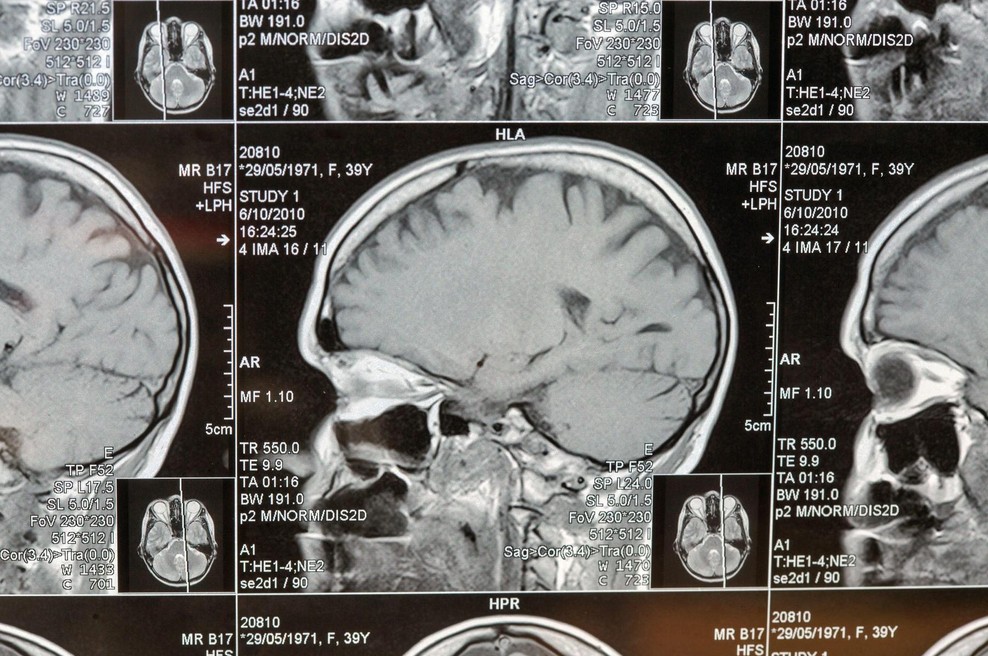

Nevrokirurgi uporabili umetno inteligenco in obstali kot paralizirani: kar so našli v človeških možganih, spremeni vse,  kar smo vedeli (foto: Profimedia)

Več desetletij so nevroznanstveniki verjeli, da lahko človeške možgane razdelimo na približno 50 območij, od katerih ima vsako svojo nalogo: eno za spomin, drugo za strah, tretje za načrtovanje. Toda nova raziskava, izvedena na univerzi v Kaliforniji (UCSF) in Inštitutu za možganske znanosti Allena, je pokazala, da so se motili! Človeški možgani imajo kar 1300 skritih predelov, ki do zdaj niso bili nikoli kartirani.

Odkritje, objavljeno v reviji Nature Communications, je omogočil umetno inteligentni sistem po imenu Cell Transformer, zasnovan po istem principu kot ChatGPT. Toda namesto da bi se učil jezika, se je ta algoritem učil "jezika celic". Prepoznaval je, kako se posamezne možganske celice med seboj povezujejo in tvorijo kompleksno mrežo.

"Z umetno inteligenco smo prvič videli meje med regijami možganov z natančnostjo, ki je človeško oko ne bi moglo doseči," je pojasnil vodilni raziskovalec dr. Reza Abbasi-Asl. Sistem je na podlagi milijonov podatkov iz možganov miši ustvaril visokoločljiv zemljevid, na katerem je razkril več kot 25-krat več področij, kot jih poznajo tradicionalni možganski atlasi.